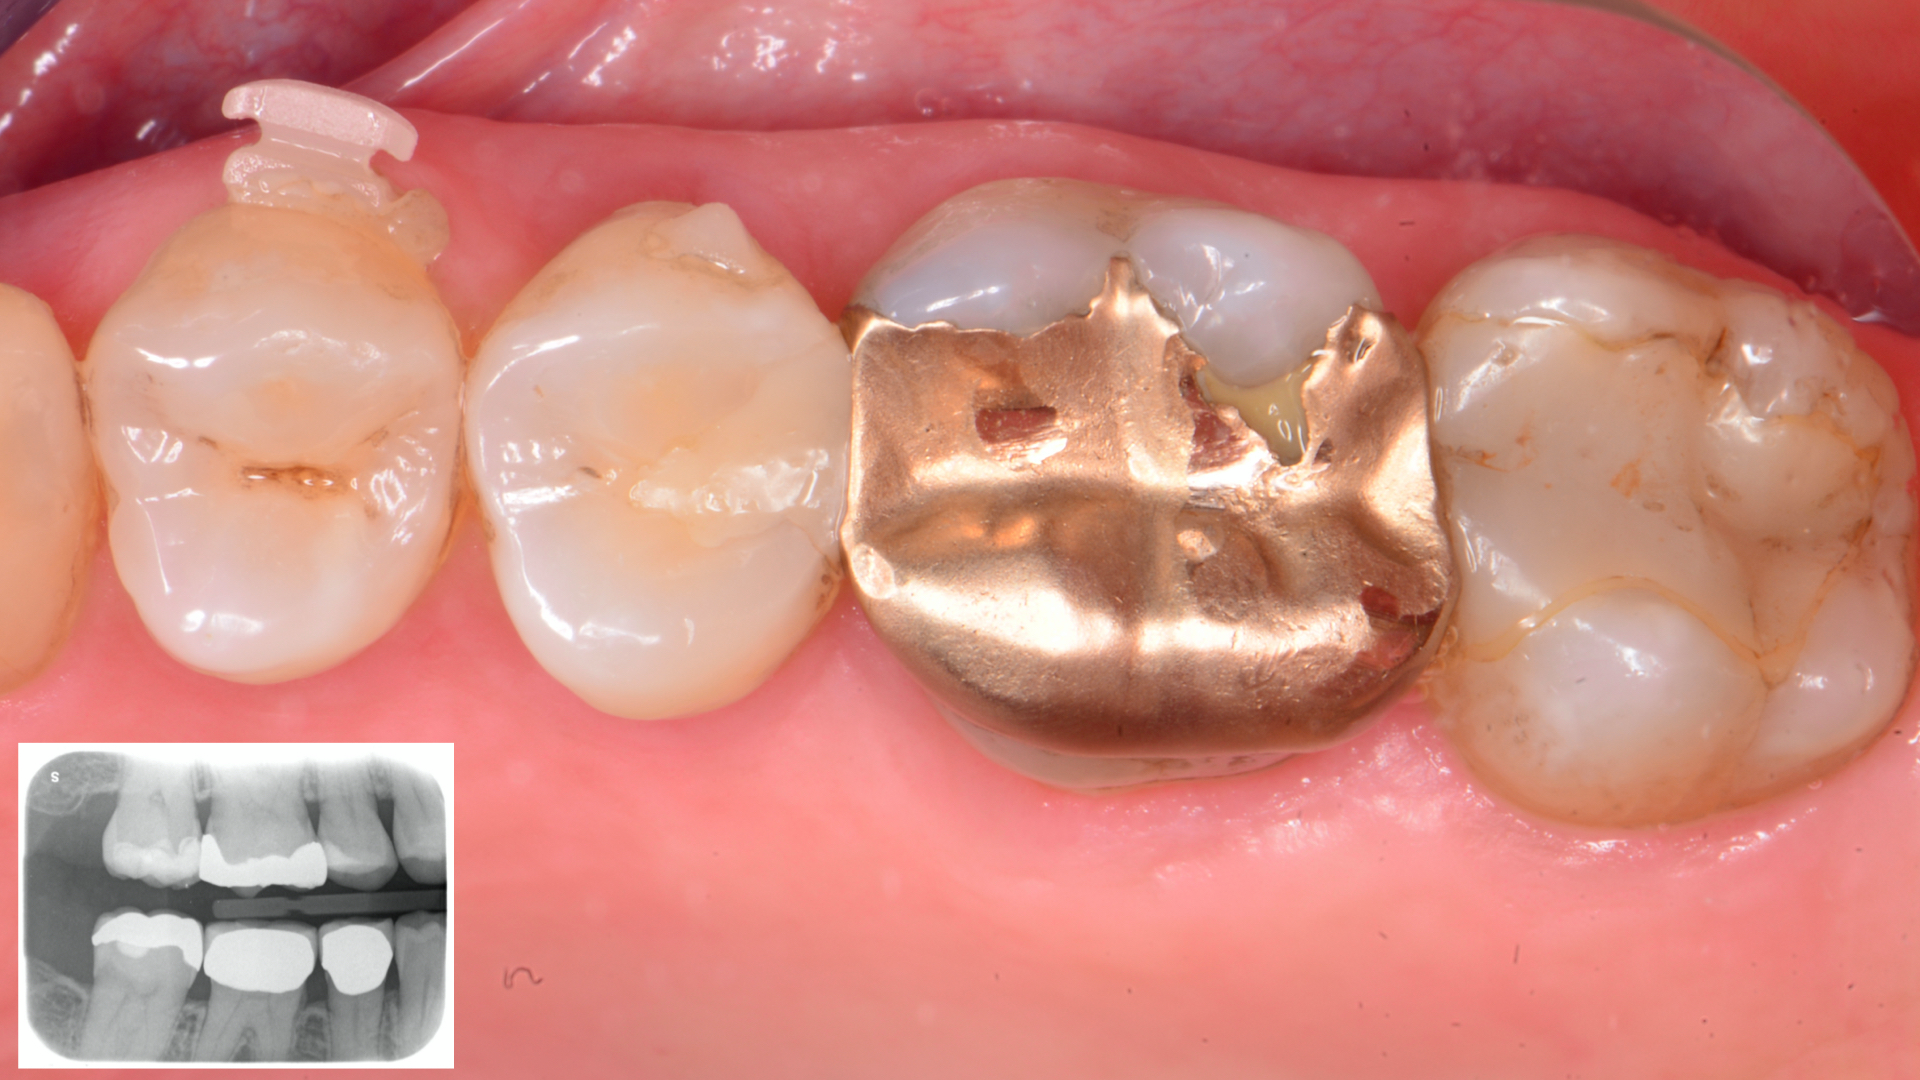

Il paziente si è presentato alla nostra osservazione lamentando fastidi in masticazione e sensibilità termica nell’arcata superiore destra.  Dopo  esame  clinico  e  radiografico  si  sono  evidenziate lesioni cariose a carico degli elementi 1.7-1.6-1.5.-1.4 Si è optato per un restauro diretto in composito con approcci minimamente invasivo negli elementi 1.4 ed 1.5 . A carico degli elementi 1.7 e 1.6 sono stati invece programmati restauri indiretti in composito ibrido a ricopertura cuspidale. Questa scelta è stata presa dopo una accurata valutazione biomeccanica delle strutture residue.

1

2

Fig.1 Situazione preoperatoria. Visione Occlusale (rx allegata)Fig.2 Isolamento del campo operatorio mediante diga di gomma